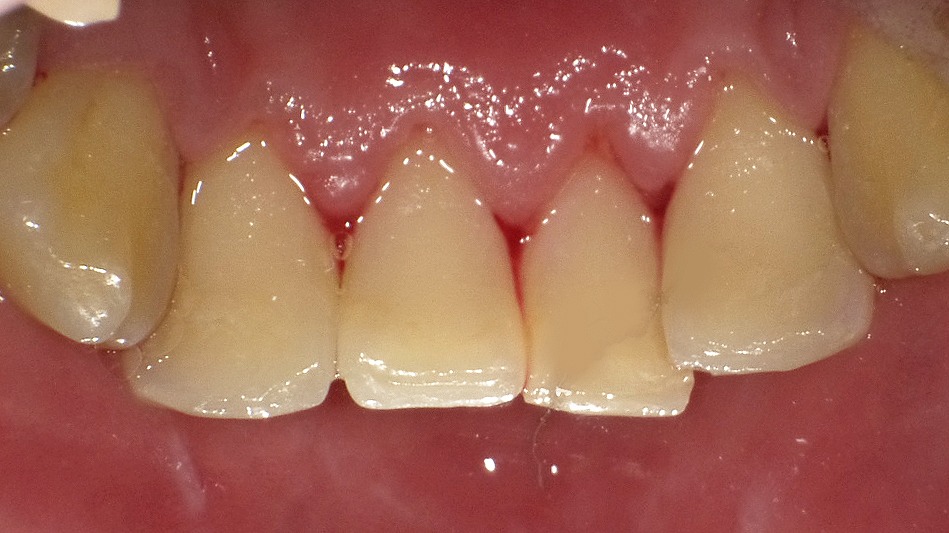

歯石除去前後でわかる歯ぐきと全身への影響

歯石が付着し歯肉が腫脹している状態(治療前)と、歯石除去後を示した同一症例です。歯周病による慢性的な炎症は、歯周病菌や炎症性物質が血流に乗って全身へ広がり、動脈硬化や心血管疾患のリスクを高める可能性があるとされています。歯石除去を中心とした歯周治療は、歯を守るだけでなく、全身の健康を考えるうえでも重要な治療です。